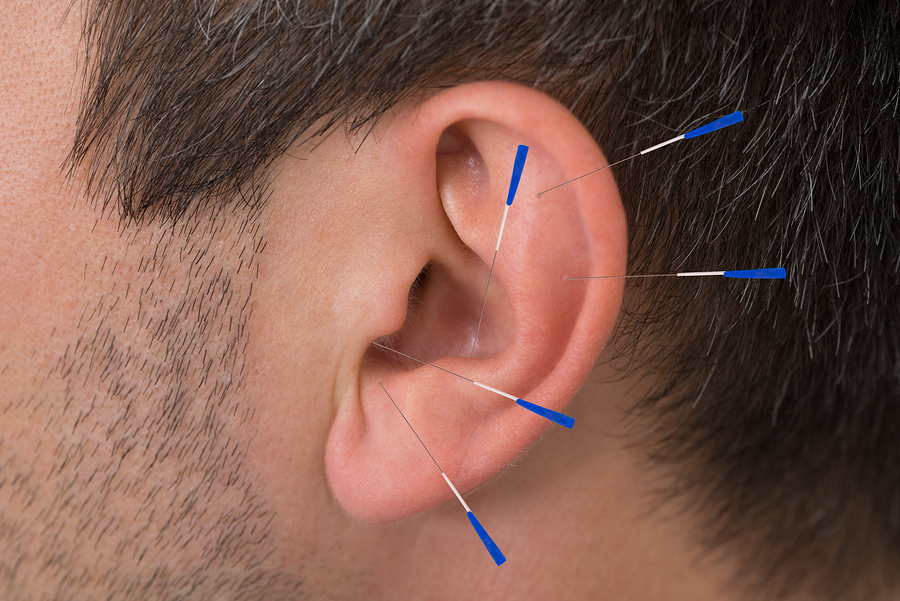

Ear Acupuncture Treatment

Ear acupuncture focuses on specific micro-points in the ear that correspond to different organs and body systems. It is a powerful therapy often used for quick pain relief and stress management.

Common Uses:

Anxiety and stress

Insomnia

Addiction control support

Headache relief

Hormonal imbalance